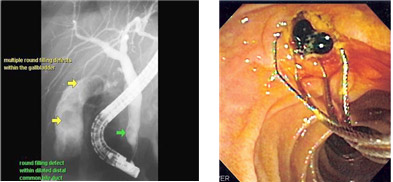

ERCP(내시경적 역행성 췌담관 조영술)란 총담관에 삽입한 내시경을 통해 담도계 및 췌관에 조영제를 주입하여 X선 촬영을 하는 수면 내시경 검사입니다.

내시경을 이용한 담췌관 촬영술이며,

담도 및 췌장 등의 장기에 발생하는 각종 질환(총담관담석증, 담관염, 담관암, 췌장염, 췌장암, 바터팽대부암 등)의 진단과 치료를 위해 시행합니다.

1. 장운동을 억제하기 위한 주사를 맞고 십이지장 거품 제거제를 복용합니다.

2. 목을 약하게 마취시킵니다.

3. 목과 위를 거쳐 십이지장까지 내시경을 집어넣습니다.

4. 담관 및 췌관 안에 조영제를 주입함으로써 영상을 얻습니다.

1. 담도 폐쇄에 의한 황달

2. 총담관결석에 의한 급성 담관염

3. 악성 담관 폐쇄(담관암, 췌장암 등)에 의한 급성 담관염

4. 급성 담석성 췌장염

5. 원인을 알 수 없는 재발성 췌장염

6. 담관 손상에 의한 담즙 누출

7. 외상에 의한 췌장 손상